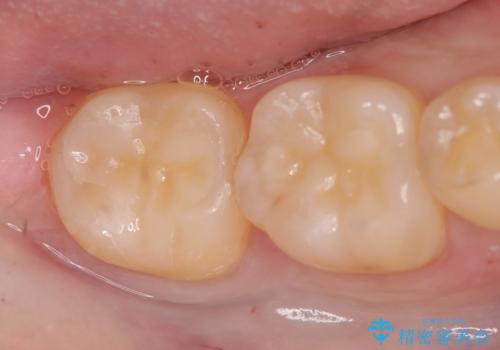

広範囲にわたる虫歯をセラミックで治療